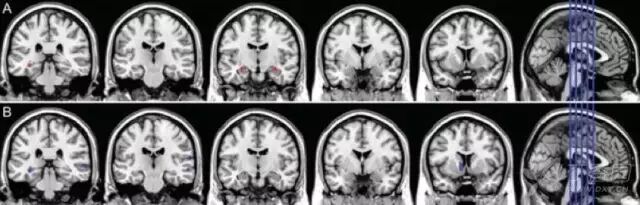

3. 结构磁共振(sMRI)

sMRI 可测量区域性或全脑体积大小,反映因细胞损伤、轴突退变、突触失调引起的结构萎缩。最早出现并进行性加重的内侧颞叶结构萎缩可能是 AD 早期出现的特征性改变,其中海马萎缩,被认为是 MCI 进展到 AD 痴呆的最佳标志物。

研究还发现,AD 早期人群的皮层灰质、内嗅皮层和海马旁回也存在萎缩。MCI 患者可出现皮质厚度变薄和全脑体积变小,可用于预测 MCI 向 AD 的转化。

2011 年 NIA-AA 诊断标准将 sMRI 作为 AD 神经损伤标记物之一;然而 2014 年最新的 IWG-2 标准认为 sMRI 可能更适合用于测量和监测疾病过程。

图 4  正常对照组(CN)、aMCI 和 AD 患者的海马体积结构 MRI 成像 3